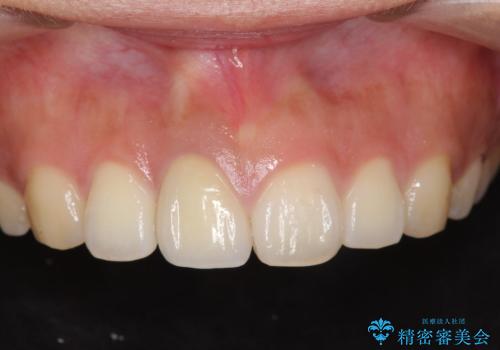

[ 再生治療・歯周外科・小矯正・セラミック補綴 ] 前歯の歯周病治療

担当医 大元洋佑